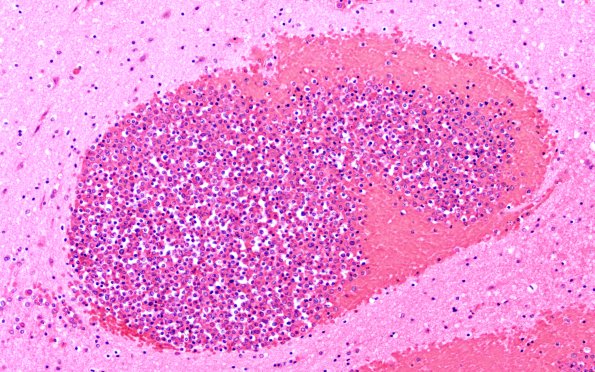

Washington University Experience | NEOPLASMS (HEMATOLYMPHOID) | Granulocytic Sarcoma | 4B1B Case 4E 20X

Multiple hemorrhages appreciated grossly in cerebral cortex and brainstem prove on microscopic examination to consist of a rim of fresh hemorrhage surrounding a pure collection of white cells most of which appear to be myeloblasts. These lesions have a predilection for the area of the grey-white junction. There is no reaction to these aggregates of leukemic cells by the surrounding neural elements. (Dilated vessels containing sheets of leukemic cells are easily found; additionally, some of the nodules of myeloblasts contain remnants of a vascular wall. There are subarachnoid collections of leukemic cells over cerebral cortex and cerebellum. (H&E)